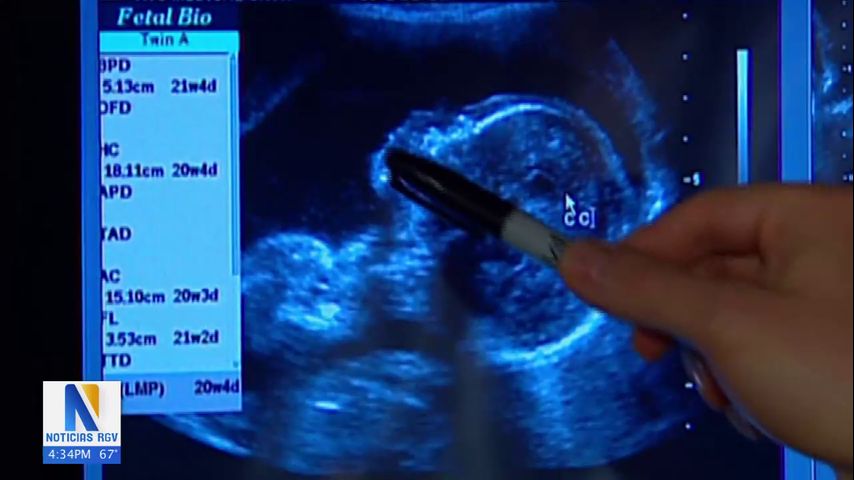

Hace 13 años, cuando Amy Desantis dio a luz a gemelos, no tenía idea que uno de ellos tenía síndrome de down y un defecto en el corazón.

Los gemelos de Desantis acaban de cumplir 13 años y, a pesar de los desafíos, su hijo está progresando.